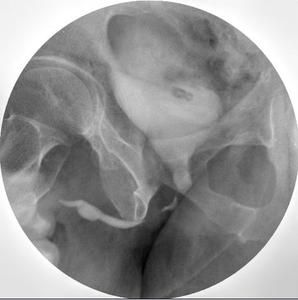

排泄法尿道造影

(一)適用範圍

本法尿道全程處於鬆弛狀態,對觀察尿道狹窄,特別是後尿道狹窄,瘺管及後尿道先天性瓣膜畸形,更為滿意。

(四)具體操作方法

消毒尿道口。將導尿管插入膀胱。抽盡尿液。注人造影劑至膀胱完全充盈,病人感覺下腹脹及開始有排尿感時停止。

(五)攝片體位

1.立位斜位。抽出導尿管,令病人用力快速排尿,在排尿速度最陝時暴光。

2.亦可於IvP終了時,令病人排尿,在排尿過程中攝片,體位同上。